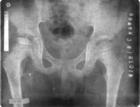

吉林市股骨頭壞死專科醫院吉林省吉林市股骨頭壞死專科醫院是由骨傷科專家、主任醫師、吉林省名中醫、國務院特殊津貼獲得者黃克勤教授創建、領導的專家群體,融科研、教學、臨床為一體,採用黃克勤教授研製的高科技專利成果“股骨頭壞死新療法”非手術、無損傷、無痛苦,中醫中藥治療股骨頭壞死。其療法特點以養氣血、續筋骨,益髓填精,扶正固本,惟朽骨生新骨,使其筋脈肉和其順達,骨壯筋柔,在生物學修復過程中保存髖關節結構的完整性,重建股骨頭結構,改善髖關節功能,從而提高病人生活質量。該療法符合現代國際化無損傷、安全可靠治療疾病的流行趨勢。

吉林市股骨頭壞死專科醫院“股骨頭壞死新療法”包括:“股骨頭壞死計算機圖像診斷系統”、“股骨頭壞死治療儀”、“承載丸系列中藥”和“髖關節動態模造方法”、“髖關節調整器”、“藥膳”、“藥浴”、光波浴療法等綜合方法。形成了獨特的中醫醫療體系,對股骨頭壞死的治療突破醫學定論,提出了新理論、新手段。研究發現股骨頭壞死與骨結構改變有關,是由於某種致病因素使股骨頭的結構發生破壞、變異,骨內微循環受擠壓、斷裂、捲曲、阻塞,致局部骨組織缺血,骨細胞死亡,骨小梁破壞,股骨頭壞死。